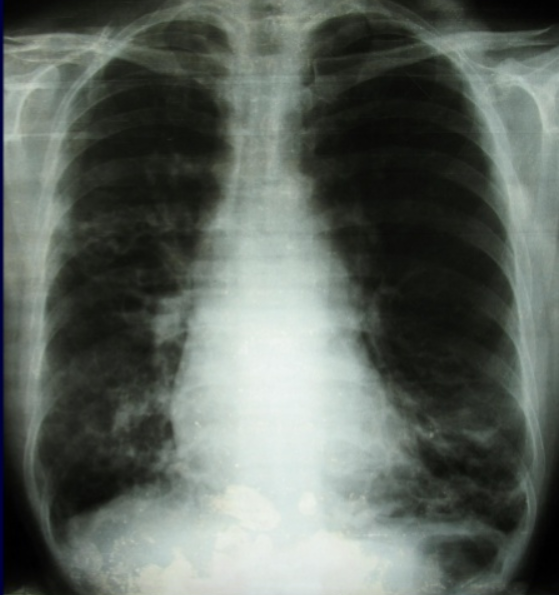

- Trên phim X quang phổi chuẩn: có thể thấy các dấu hiệu gợi ý hoặc khẳng định chẩn đoán giãn phế quản trong một số trường hợp giãn phế quản nhiều và nặng. Tuy nhiên chẩn đoán xác định giãn phế quản thường phải dựa vào phim chụp cắt lớp vi tính lớp 1mm, độ phân giải cao

Hình ảnh giãn phế quản trên X quang:

- Thành phế quản tạo thành các đường song song (đường ray).

- Thể tích của thuỳ phổi có giãn phế quản nhỏ lại, các đường mờ mạch máu phổi xít lại với nhau nếu có xẹp phổi.

- Có các ổ sáng nhỏ giống hình ảnh tổ ong, có thể có ổ sáng với mực nước ngang kích thước thường không quá 2 cm

- Hình ảnh viêm phổi tái diễn vào mùa lạnh xung quanh khu vực giãn phế quản.

- Các đám mờ hình ống biểu hiện của các phế quản bị lấp đầy chất nhầy, mủ.

- Khoảng 7 - 30% trường hợp chụp phổi chuẩn không thấy gì bất thường.